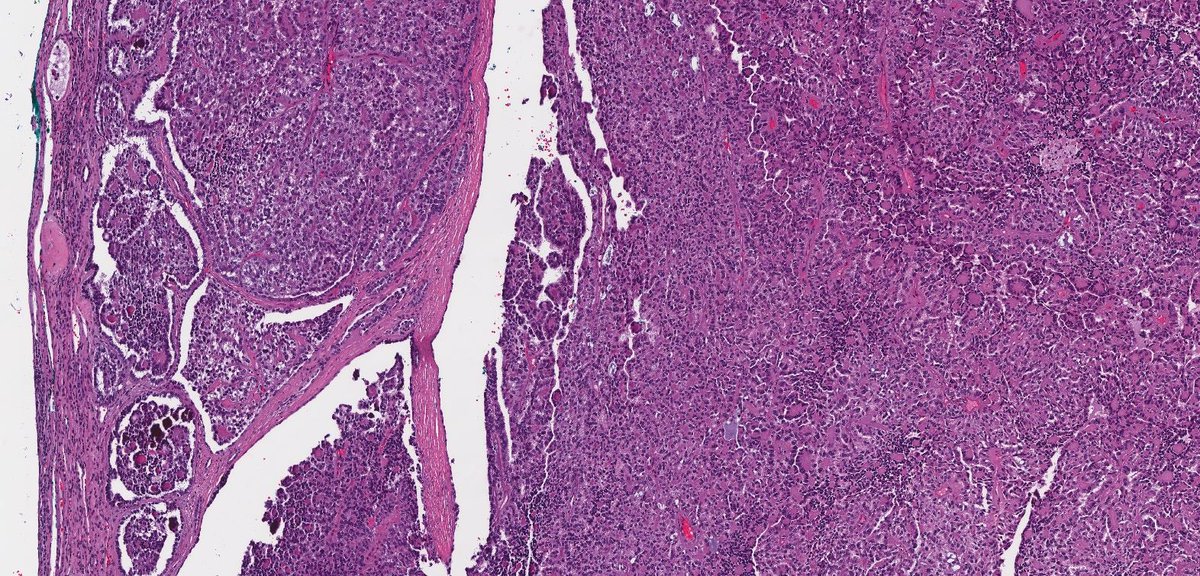

☝🏼papillary renal cell carcinoma (not shown)

✌🏼papillary adenoma (left), papillary neoplasm reverse polarity (right)

#gupath #pathtwitter #pathoutpic

#twoforoneseries radical nephrectomy☝🏼well-circumscribed, variegated yellow-orange to red-brown, hemorrhagic mass

✌🏼incidental, irregular gray to yellow to slightly orange lesions (>15) throughout the kidney, ranging from minute to 0.8 cm in size